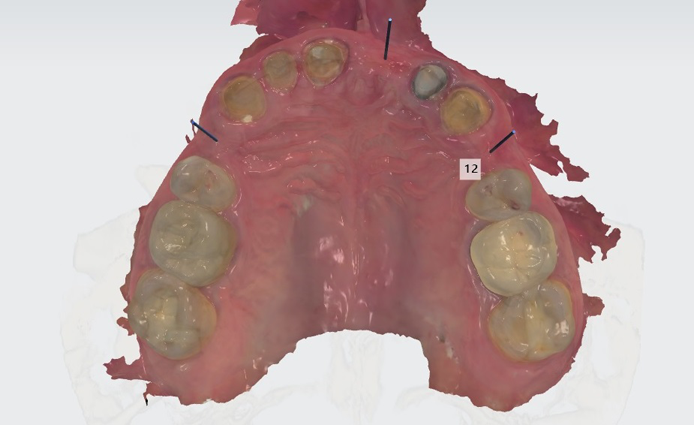

2. This patient was then scanned with a 3Shape TRIOS intraoral scanner. The resulting color scan is shown in Figure 3. This scan was then pulled into 3Shape Implant Studio and aligned with the DICOM data, and placement of three BioHorizons Implants was planned. Tooth position #12 was planned with a 3.0 mm x 15.0 mm implant. In Figure 4 you can see the root formations for teeth 11 and 13 created a limited space situation.

Fig. 3 Fig. 4